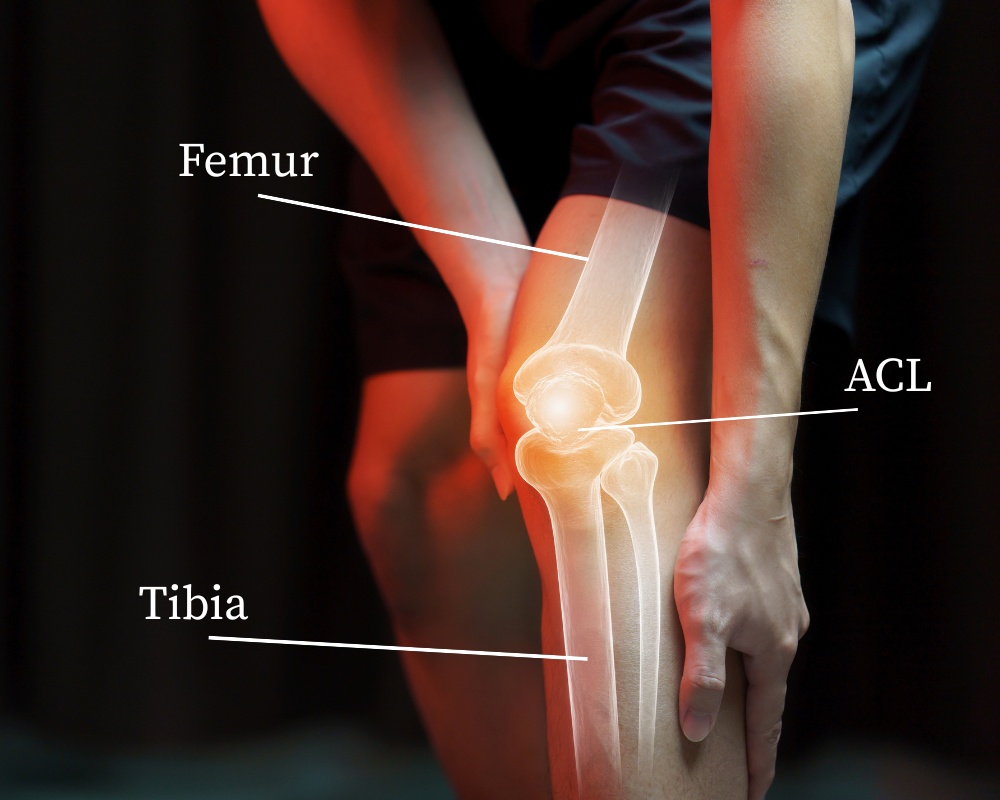

What the ACL Does, and Why it Matters

The ACL is a strong band that connects your thigh bone (femur) to your shin bone (tibia). It keeps the tibia from sliding too far forward and helps guide your knee’s rotation.

This control matters most when you twist, pivot, or make quick changes in direction. When the ACL tears, that fine control is lost.